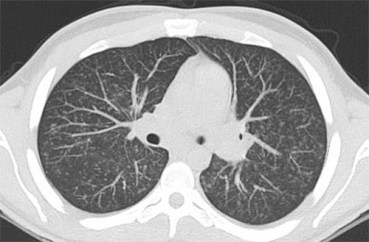

Las figuras 1, 2 y 3 ilustran ejemplos de signo, hallazgo y patrón.

Figura 3. Ejemplo de patrón. La presencia de múltiples nódulos intersticiales, de pequeño tamaño y distribución difusa define al patrón miliar, que puede estar causado por enfermedades granulomatosas infecciosas, y no infecciosas, sarcoidosis, neumoconiosis, metástasis, etc. En este caso se trataba de un paciente VIH + con tuberculosis miliar.